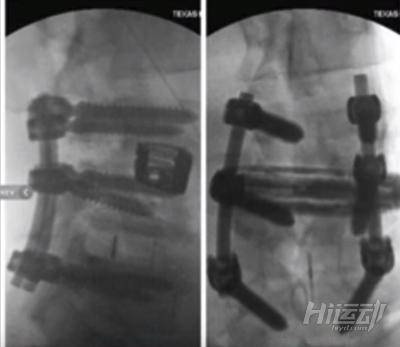

但自從退出競技比賽以來,羅尼?庫爾曼一直在掙扎著處理各種健康問題。至今,他已經進行了6次手術,還有一個手術等待著他。

這位史詩級的健美運動從2007年開始就不斷地進行手術來修復自己的身體,其中,有好幾段時間的手術導致羅尼連走路都無法完成。

2007年12月 - L4-L5椎間盤切除術

2011年7月 - L3-L4椎間盤減壓術

2011年12月 - 頸部C4-C5-C6的融合手術

2014年7月 - 左髖關節置換安裝2個螺絲

2014年8月 - 右髖關節置換安裝4顆螺絲

2015年7月 - L3-L4椎間盤的融合

剛過完新年不久,“祖師爺”1月12日又要進行一次背部手術。上次的背部手術是他經歷過最為痛苦的手術:6個脊柱被醫生移除。

而這次手術將更為痛苦和驚悚:由于之前的手術導致背部傷疤過多,這次手術只能從腹部進行脊柱手術,而醫生不得不先把他的腸子拿出來,然后再進行脊柱的手術,手術后六個月禁止進行健身訓練。